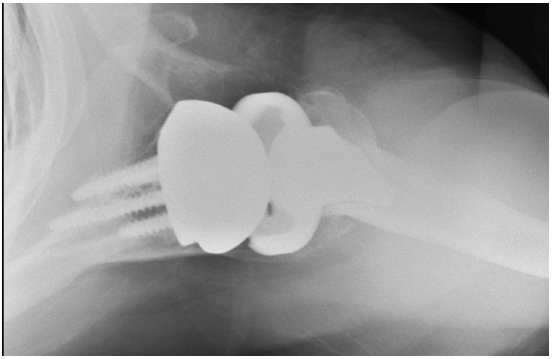

Patient 2: Primary anatomic total shoulder arthroplasty using a stemless implant.

- Active male in his 60s, retired radiologist

- Typical pain and significant range of motion limitations